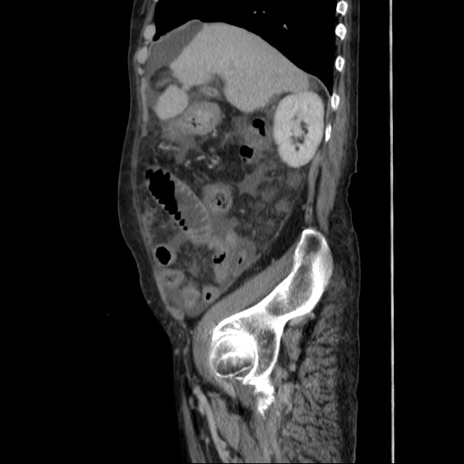

症例31(矢状断像)

【症例】80歳代 女性

【主訴】腹部膨満感

【現病歴】他院にて肝硬変にてフォロー中。1週間前から便秘、腹部膨満感、臍部腫瘤あり受診となる。

【既往歴】肝硬変

【身体所見】腹部膨隆あり、皮膚変化なし、疼痛なし。

【データ】WBC 4600、CRP 0.25